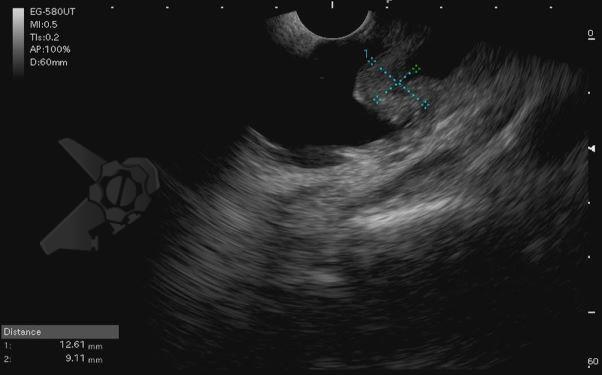

Diante da confirmação histológica de adenoma tubular com displasia de baixo grau, optado pelo estadiamento local através de ultrassom endoscópico (EUS), evidenciando lesão restrita a mucosa (sem sinais de acometimento de camada muscular) medindo 12×9 mm, com dilatação de colédoco até 9 mm e ausência de extensão intraductal.

O estadiamento deve seguir a classificação TNM e pode ser realizado por tomografia computadorizada (TC), colangioRNM, EUS e ultrassom intraductal. Nota-se a superioridade do EUS na avaliação do T (principalmente em lesões maiores do que 2 cm e T1) e da colangioRNM na avaliação do N. Ademais, a avaliação da extensão intraductal da lesão se faz necessária para definição do tratamento4.